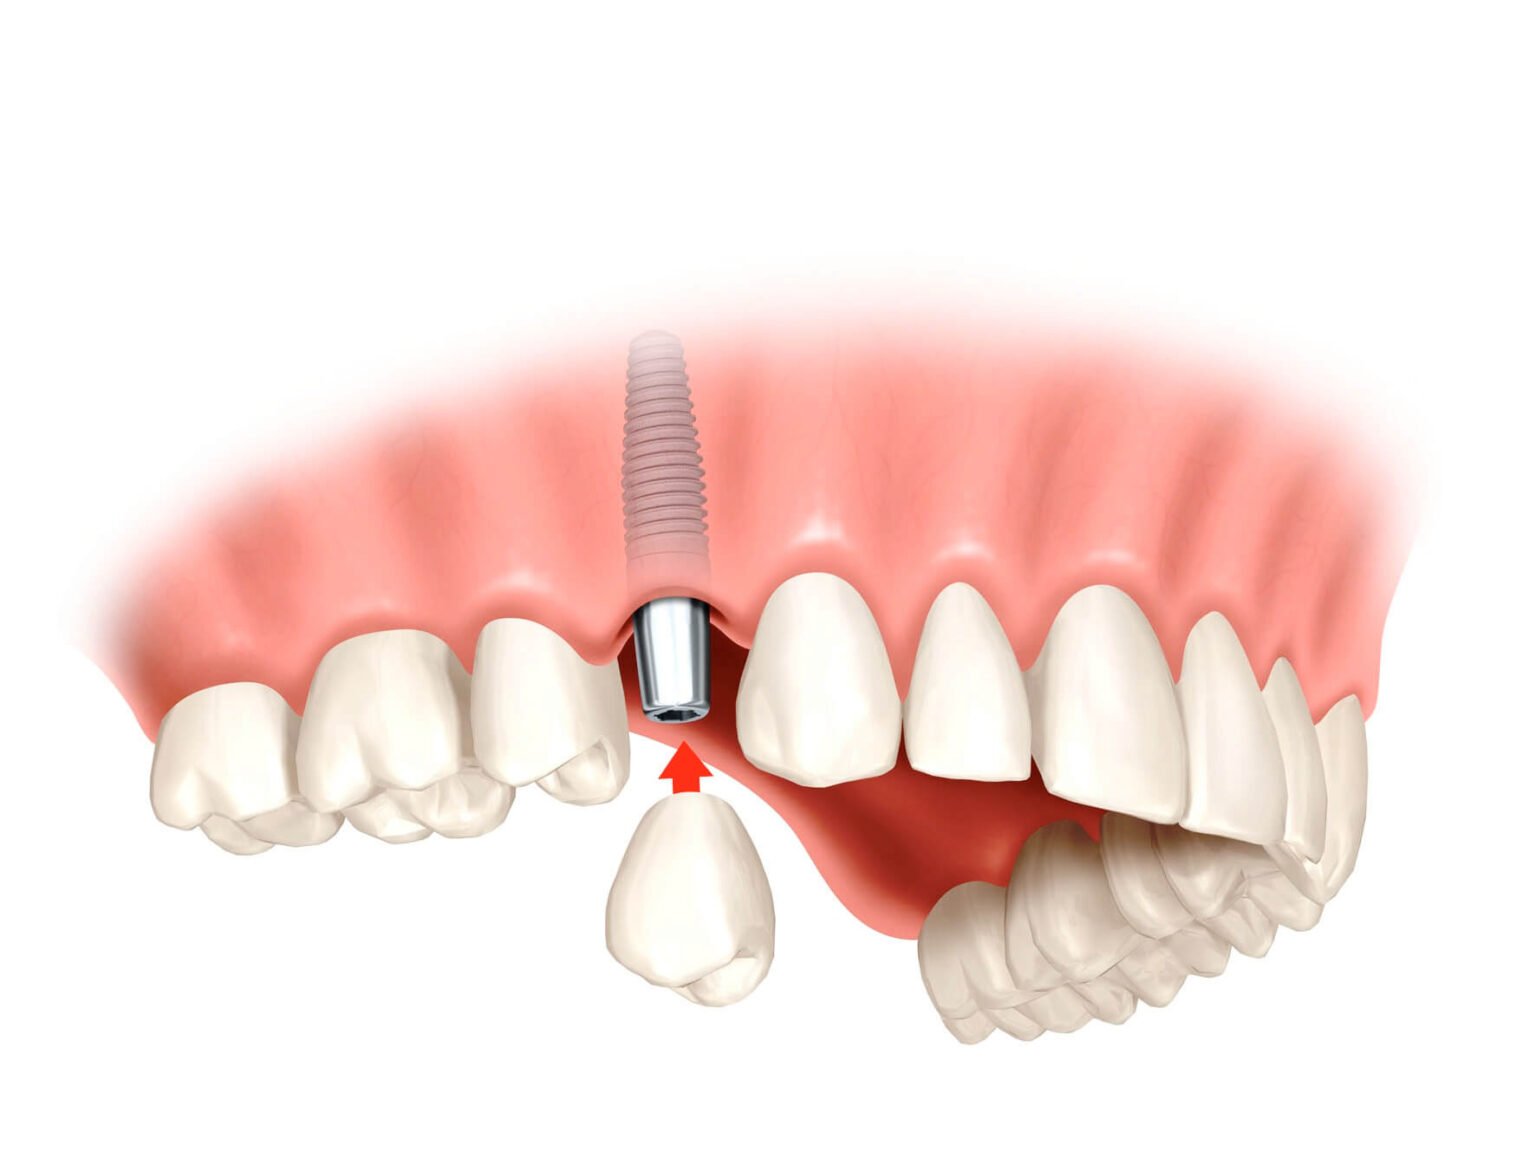

Однако независимо от продвинутых технологий и методик имплантации, качество использованных имплантатов остается фундаментальным аспектом. В 2023 году появились новые поколения имплантатов, которые отличаются высокой прочностью, биосовместимостью и эстетической привлекательностью. Использование высококачественных имплантатов помогает минимизировать риск осложнений и обеспечивает долговременную функциональность и надежность замещенных зубов.

Одним из существенных преимуществ имплантации зубов в 2023 году является также возможность индивидуализации процедуры под каждого пациента. Современные имплантаты могут быть адаптированы к уникальным потребностям пациента, учитывая его анатомические особенности и эстетические предпочтения. Это позволяет достичь наилучших результатов и удовлетворить требования даже самых требовательных пациентов.

В заключение, имплантация зубов в 2023 году представляет собой сложную и многостороннюю процедуру, в которой применяются передовые технологии, такие как компьютерная диагностика и навигационные системы. Однако успех процедуры также зависит от качества использованных имплантатов. Пациенты и стоматологи должны стремиться к использованию высококачественных имплантатов, которые обеспечивают надежность, функциональность и эстетическую привлекательность замещенных зубов. Благодаря постоянному развитию стоматологической технологии и материалов в области имплантации зубов, пациенты могут получить качественное восстановление утраченных зубов и вернуть свою здоровую и красивую улыбку.